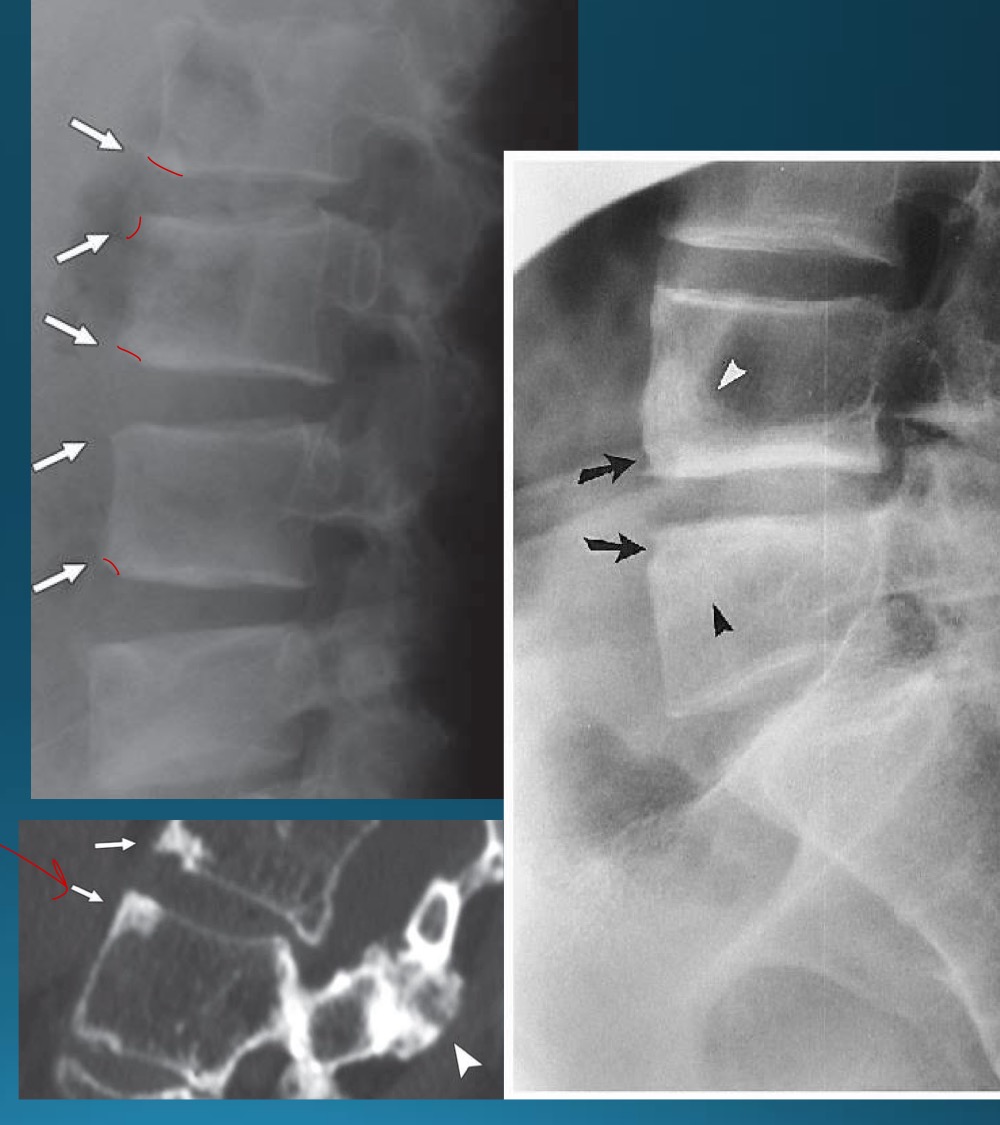

what type of seronegative arthritis is marked by marginal syndesmophytes?

AS

what is the difference between AS and DISH ossification between vertebra

facet joints are ankylosed in AS

appearance of spine in AS AKA

bamboo spine

what do you call this sign? what diangosis is this apart of?

trolley track sign

dagger sign

andersson lesion